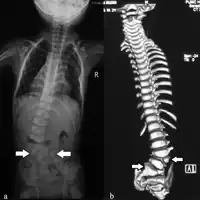

a) Spinal X-ray b) and CT scan (B) indicate left hemivertebra L3/L4, and hemivertebra L5/S1 fused with S1 vertebra ( arrows)

Vertebral anomalies, or defects of the spinal column, usually consist of small (hypoplastic) vertebrae or hemivertebra where only one half of the bone is formed. About 80 percent of patients with VACTERL association will have vertebral anomalies.[6] In early life these rarely cause any difficulties, although the presence of these defects on a chest x-ray may alert the physician to other defects associated with VACTERL. Later in life these spinal column abnormalities may put the child at risk for developing scoliosis, or curvature of the spine.